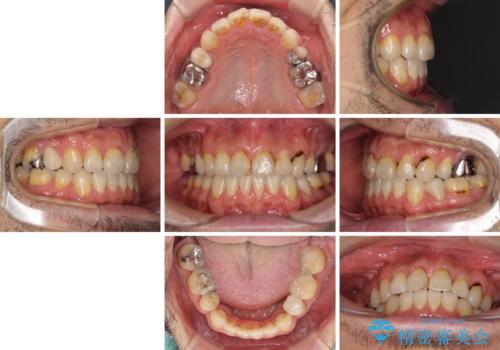

むし歯や銀歯が気になる 後戻りの再矯正治療とむし歯治療

- むし歯による奥歯の痛みを気にして来院された患者様です。

神経にまでむし歯の及んでいる歯や、既に根管治療がされている歯に痛みがあったため、まずは根管治療を行うこととしました。

その後、以前行った抜歯矯正の後戻りをインビザライン・ライトにより改善し、むし歯や銀歯はオールセラミッククラウンにて補綴治療することとしました。

痛みは速やかに引き、銀歯や黒く変色したむし歯がセラミッククラウンで自然な色合いに仕上がり、患者様には大変満足していただきました。